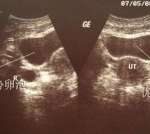

通常我们比较担心宝宝出现髋关节的发育不良的问题,就比较关注宝宝双侧大腿纹路对称的情况。从图片上看,纹路对称,但可能深浅不一。图片不能说明问题。实在担心的话,建议去做一个髋关节的超声,可以解除疑虑。另外宝宝的体重是非常好的。六个月,身长65公分。正常六个月的男孩儿,身长应该在68公分。宝宝年龄比较小,可能测量存在一个误差,目前身高不能说明实际的问题,需要动态观察。

如果发现宝宝臀纹(腿纹)不对称,家长可以用这两个方法初步筛查。在宝宝平躺时,将双腿弯曲并拢,观察双膝部是否等高。握住宝宝双膝,外展双腿,是否受限。如果这种检查都是没有什么异常的情况,可以暂时不用检查的。如果有所异常,建议去医院查一下髋关节B超,如果达到6个月以后,可以拍一下髋关节x线片子。